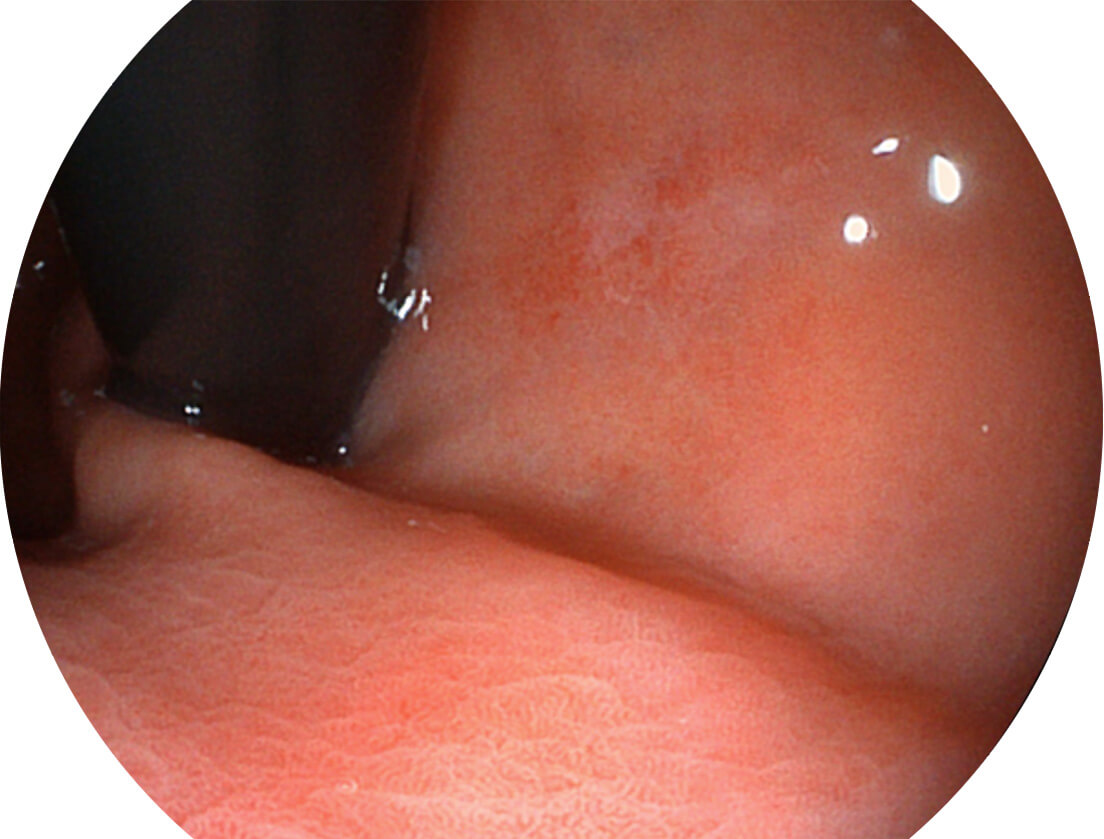

采用无损耗高清数字接口,视频输出分辨率≥1920×1080,图像清晰、细腻。

采用光路合束技术,光谱自由度高,实现了更丰富的照明模式,染色模式SFI及VIST,从远景到近景,助力消化道早期疾病诊断。

送水方向与手术器械方向,两者更贴合,能快速冲洗黏膜表面的粘液及出血,发现病变和出血点。